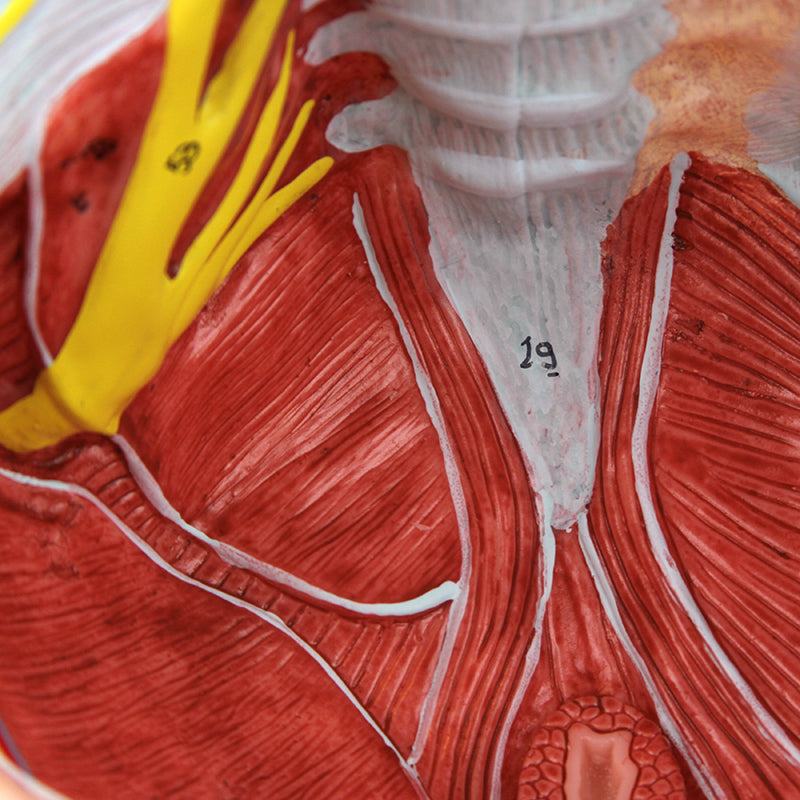

女性骨盤モデル(靭帯、血管、神経、骨盤底筋付き)

この実物大の女性骨盤は、仙腸靭帯、骨盤底筋、神経網および仙骨血管とともに、骨盤の外性器および内性器の構造を手描きで示しています。筋肉や靭帯の筋理を細かく描写しており、このモデルに高品質で詳細な印象を与えています。このモデルは女性の骨格系を理解するための優れた学習教材であり、すべての学生に適しています。さらに、神経痛、筋肉の緊張、靭帯の損傷を患者に説明する際にも役立ちます。拡張現実を用いたインタラクティブな三次元解剖モデルと併用することで、学習を促進し支援する優れたツールとなります。このプラットフォームは、学生が個々の器官の構造を比較・対照しながら解剖モデルの比較分析に取り組むことを可能にします。また、この取り組みは継続教育の場を提供し、すべての学生が解剖学、生理学および病理生理学の知識を深める機会を提供します。

女性骨盤モデル(靭帯、血管、神経、骨盤底筋付き)

この実物大の女性骨盤は、仙腸靭帯、骨盤底筋、神経網および仙骨血管とともに、骨盤の外性器および内性器の構造を手描きで示しています。筋肉や靭帯の筋理を細かく描写しており、このモデルに高品質で詳細な印象を与えています。このモデルは女性の骨格系を理解するための優れた学習教材であり、すべての学生に適しています。さらに、神経痛、筋肉の緊張、靭帯の損傷を患者に説明する際にも役立ちます。拡張現実を用いたインタラクティブな三次元解剖モデルと併用することで、学習を促進し支援する優れたツールとなります。このプラットフォームは、学生が個々の器官の構造を比較・対照しながら解剖モデルの比較分析に取り組むことを可能にします。また、この取り組みは継続教育の場を提供し、すべての学生が解剖学、生理学および病理生理学の知識を深める機会を提供します。